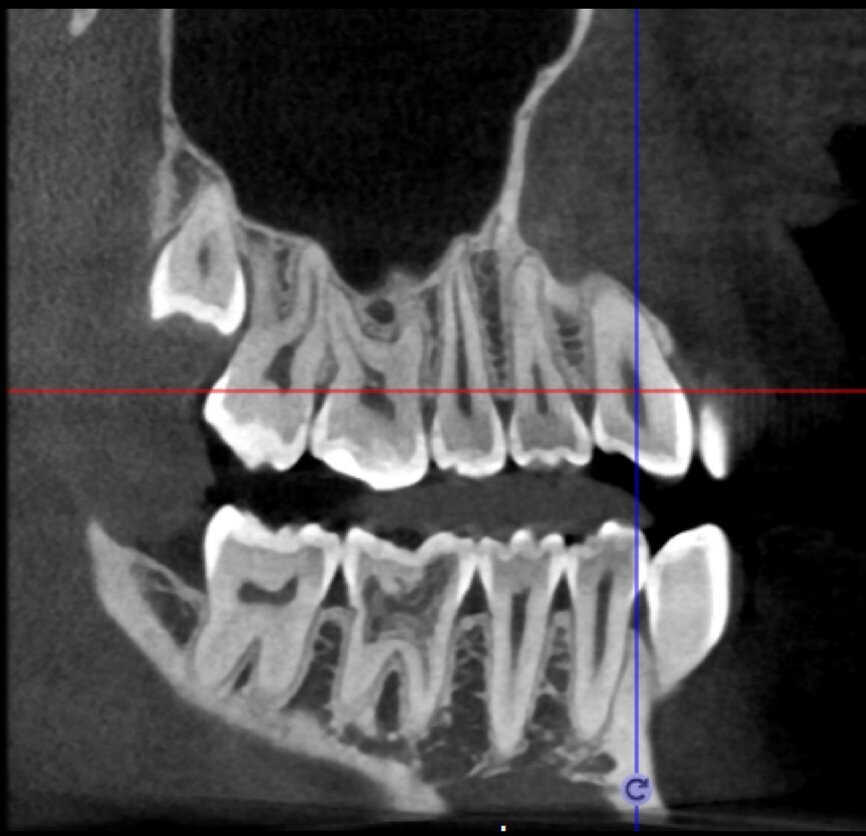

The case with which I would like to start my clinical review is a perfect example of how difficult it is to establish the origin of the patient’s symptoms on the basis of an intraoral radiograph alone. Not only does the 2D study fail to establish with certainty the presence of a lesion, but more importantly, it is impossible to establish the size, morphology and type of the lesion. An analysis of the 3D imaging, however, provides a clear picture of the clinical situation: the coronal and sagittal slices revealed the presence of a large lesion extending from the apex of the mesial root of this molar to the furcation, while the axial slices allow us to conduct a precise analysis of the endodontic anatomy and, in particular, the shape of the mesial root, which in this case was fused with the palatine root. A full overview of the case can, therefore, guide the decision-making process and direct the treatment plan towards a specific type of treatment (Figs. 1–4).